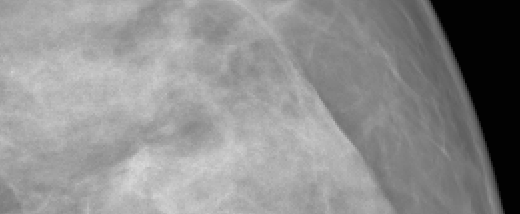

4.4 Super-Resolution

Image super-resolution (SR) refers to the task of reconstructing high-resolution (HR) images from their low-resolution (LR) counterparts [40]. In this work, SR is explored as a way to generate HR mammograms from the LR images, which can be synthesized using a standard low-resolution DDPM. Since no existing SR approaches were specifically developed for mammography, MAMBO was compared against bicubic interpolation and three general-purpose state-of-the-art SR models: AuraSR [13], DDNM [39], and LDM-SR [31].

AuraSR is used as-is, without any additional training. DDNM, in contrast, was pretrained on mammography images. Two versions of the LDM-SR model were evaluated: the original model, pretrained on the OpenImages dataset, and a second version, pretrained on mammography images, to adapt the model to the target domain. In the latter case, the original LDM-SR training procedure is followed for training both the first-stage autoencoder model (with VQ regularization) and the second-stage diffusion model (U-Net). Separate models were trained for the RSNA and VinDr datasets.

All metrics were calculated using real mammograms. Most SR models cannot upscale to arbitrary resolutions; therefore, all images were first zero-padded to a uniform size of pixels to preserve the resolution of the breast tissue. These padded images were then downscaled to pixels to serve as inputs for the SR models.

Due to the high computational demands of DDNM, LDM-SR, and MAMBO, generating full-resolution outputs at scale was not feasible. As a workaround, models were evaluated using independent image patches. Each input was first upscaled by a factor of 4 to generate a intermediate image. From this, a patch was extracted and then upscaled by a factor of 4. The final evaluation patch was obtained by center-cropping the resulting image.

Quantitative results presented in Tab. 4 and Tab. 5 show performance on patches extracted from images upscaled by and for the RSNA and VinDr datasets, respectively. Metrics were computed by comparing 2,540 output patches from each model against their corresponding original patches at the same spatial location. Visual comparisons of output patches for both datasets are shown in Fig. 4.

MAMBO outperforms all other methods on the RSNA dataset at the scale, achieving the best FID (21.82) and LPIPS (0.31), and showing notably better performance than the second-best, LDM-SR (Mammo), which scores 144.65 and 0.45, respectively. On the same scale for the VinDr, MAMBO delivers the best LPIPS and the second-best FID. At , AuraSR slightly outperforms MAMBO and LDM-SR (Mammo), but its performance degrades significantly at higher scales. Overall, MAMBO demonstrates the strongest performance, particularly at the native resolution used in digital mammography, delivering superior perceptual quality and fidelity.